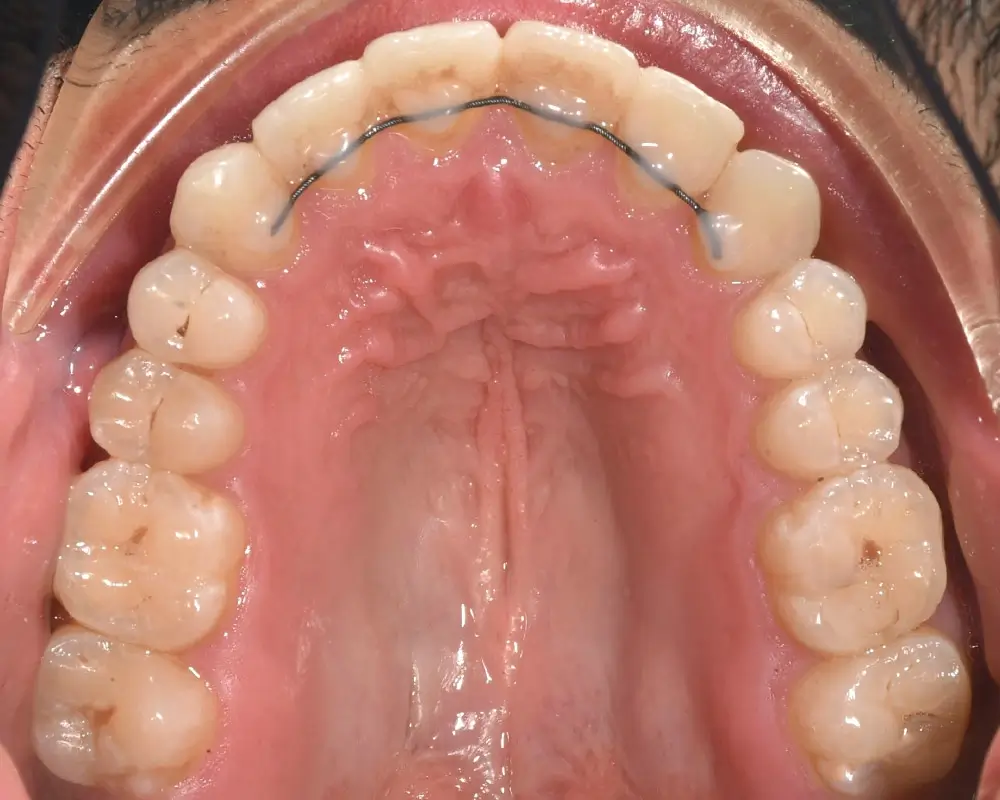

Открытый прикус - Кейс 3

Эффективность устранения дефекта прикуса посредством элайнеров FlexiLigner.

28

Количество кап НЧ

20

Количество кап ВЧ

Результаты лечения